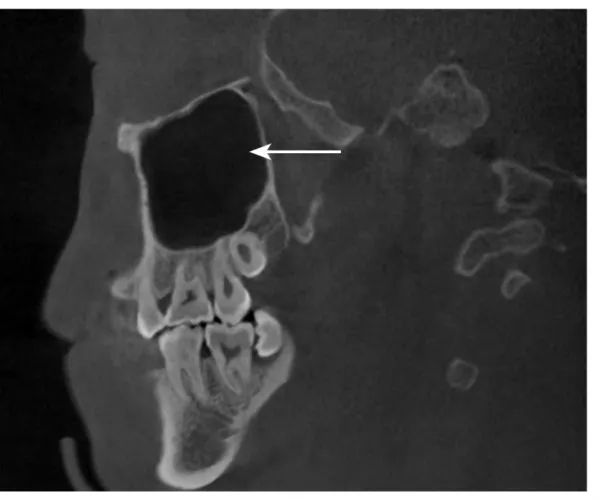

不同个体上颌窦的发育过程差异较大,可较早或较晚终止发育。上颌窦的气化程度随年龄增长而逐渐增高,儿童上颌窦腔形态与成人有差异(图1-1-18)。

CBCT示3岁儿童的上颌窦,颌骨内见正在发育的恒牙胚,窦腔形态与成人有差异